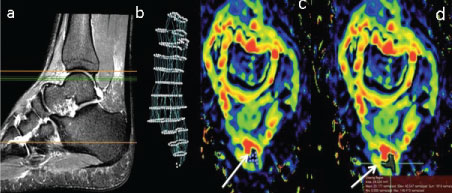

To generate ADC maps for quantitative diffusion measurements, SE-EPI-DW images were transferred to OsiriX software. The ADC measurements were calculated using an ADC plugin added to the OsiriX software. Absolute ADC measurements were quantified using the 'Grow Region', a tool that allows for similar pixel densities to be selected (e.g., 3D or 2D, and segmenting, drawing or single point ROIs) to generate ADC values of desired ROIs, which were applied on both axial and sagittal DW images of each volunteer scanned [16] (Figure 1). According to Luna, Ribes & Soto, [17], there is a lack of consistency in the methodology of generating ADC values; thus, at this stage in the research, several techniques were applied to ensure the consistency and reproducibility of generated ADC values for evaluation of healthy ATs. Each technique specification and advantage is displayed in (Table 3). All data from the scoring and ADC quantification were transferred to the statistical package for social sciences software (SPSS Inc. Ver. 20.0) to facilitate mean, standard deviation and histogram analysis of ADC values. ANOVA testing [18], was used to investigate the statistical significance between applying these different ADC measuring techniques, and whether using axial or sagittal orientation to generate ADC values present statistical differences.

Figure 1: Use of OsiriX software for semi auto (segmentation) of the AT (a): Sagittal T2W FSE + FS image of the AT to localise the area where axial images at anatomical levels c and d are selected (green lines); (b) Segmented image of the AT after 3D selection points were placed along the long axis of the AT as displayed in the sagittal image (a). (c,d): Selection of the ROI defining the AT to generate AT ADC segmentation (white arrows). View Figure 1